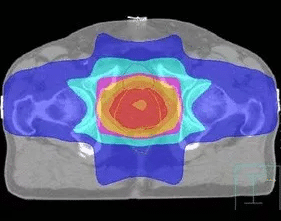

調(diào)強(qiáng)適形放射治療(IMRT)

以往放射治療使用的都是強(qiáng)度幾乎一致的射線,而腫瘤本身的厚度是不均一的,因此造成腫瘤內(nèi)部劑量分布不均。為了實(shí)現(xiàn)腫瘤內(nèi)部劑量均勻,必須對(duì)照射野內(nèi)的射線強(qiáng)度進(jìn)行調(diào)整。

IMRT技術(shù)要求把一束射線分解為幾百束細(xì)小的射線,分別調(diào)節(jié)每一束射線的強(qiáng)度,射線以一種在時(shí)間和空間上變化的復(fù)雜形式進(jìn)行照射。

IMRT通過改變靶區(qū)內(nèi)的射線強(qiáng)度,使靶區(qū)內(nèi)的任何一點(diǎn)都能得到理想均勻的劑量,同時(shí)將要害器官所受劑量限制在可耐受的范圍內(nèi),使緊鄰靶區(qū)的正常組織受量降到最低。

IMRT比常規(guī)放療多保護(hù)15% ~20%的正常組織,同時(shí)可增加20% ~ 40%的靶區(qū)腫瘤劑量。